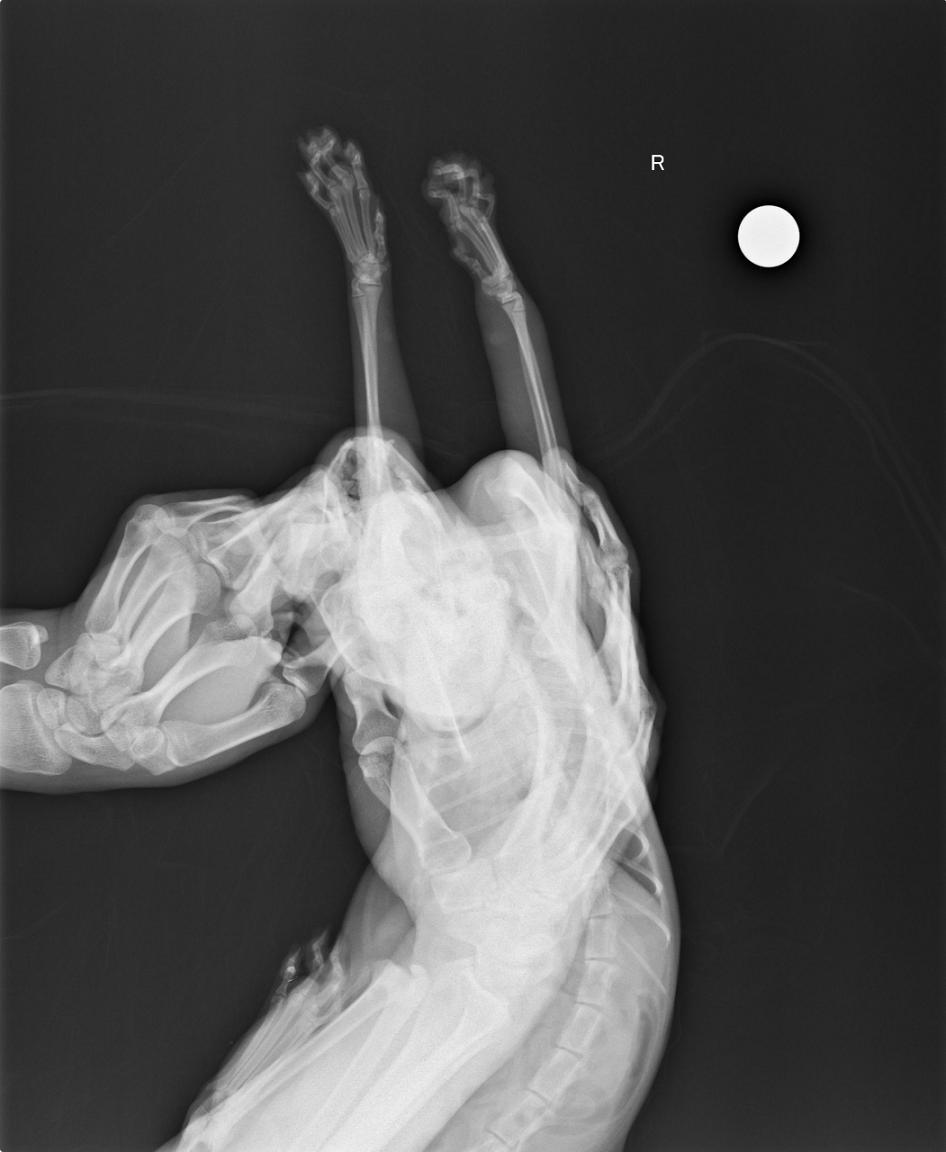

主題: 市場內的捕獸夾貓 申請者姓名: 呂錦花 花色: 申請日期: 2015-12-02 10:29:19 申請者部落格: 申請者臉書網址: https://www.facebook.com/nacat.lu 所在縣市/合作醫院: 高雄市/小新動物醫院 治療費用: 3500元 需求人數: 6人 已結案 (2023-01-18 23:38:09) 報名人員: Ying(已付款)、Ying(已付款)、yvonne(已付款)、FS.NG x2(已付款)、Sarah(已付款)、 候補人員: 動物病情說明: 國民市場不僅是市場也有販售一堆好吃的小吃.所以老鼠多.貓咪也不少....李媽最近一直在抓這區域內的貓去結紮...近下午時.接獲了一通電話.原來是市場內一戶認同李媽結紮但很低調的店家打給她的.說是有看到貓被捕獸夾抓到...李媽接到通知後趕緊處理掉手邊事情˙告一段落就衝去市場查看....確認是捕獸夾後..趕緊回家拿工具去誘捕貓. 動物近況說明: 經過醫師檢查外傷還好,但是神經反射很差,走路右前肢都會有點拖著.所以治療是先給一些抗生素跟傷口消炎消腫的針劑,另外醫師會再開促進血液循環跟神經修復的藥.希望只是被夾太久而導致血液循環不良而引起的暫時性神經問題.

貓咪帶出來時一直窩著,所以也不太能確定右前肢使用的狀況,看起來趴著的時候姿勢比較正常了..希望貓咪只是一時嚇到加上因為是在陌生的醫院所以不願行走...外傷部份大致沒問題了.醫療部分就請大家幫忙.謝謝^^